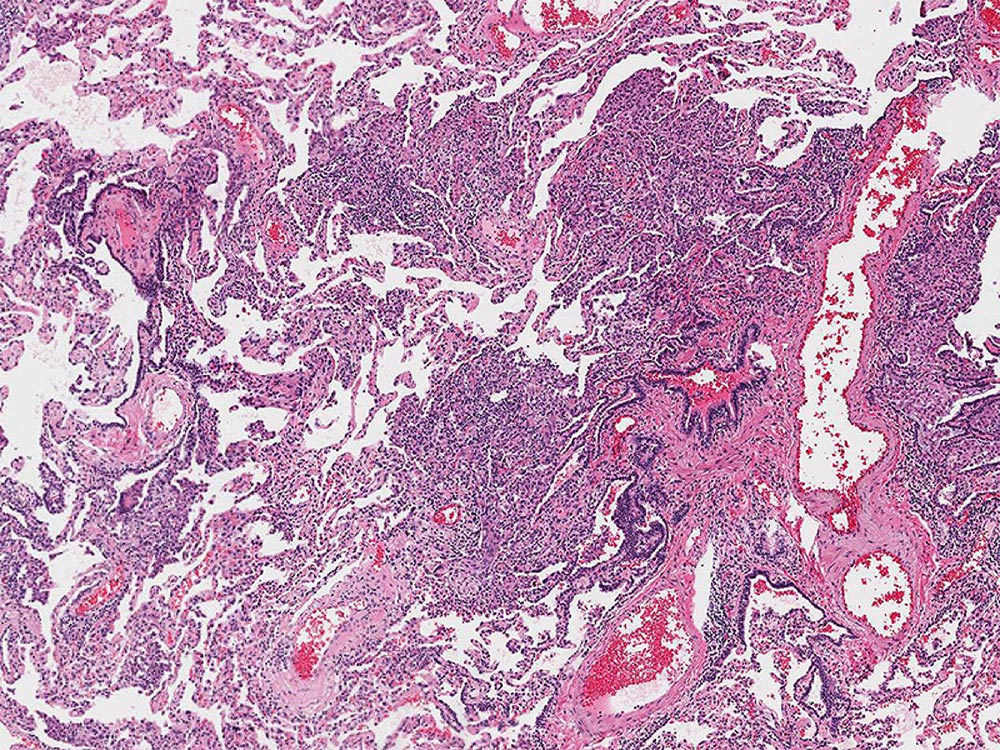

Low magnification photomicrograph showing the heterogeneous patchwork distribution of abnormalities classically seen with usual interstitial pneumonia (UIP). UIP appears as areas of fibrotic scarring with honeycomb change primarily affecting the subpleural and paraseptal parenchyma alternating with regions of normal lung tissue.

Image courtesy of and used with permission from Kirk Jones, MD.